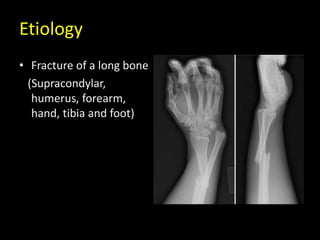

Etiology

• Fracture of a long bone

(Supracondylar,

humerus, forearm,

hand, tibia and foot)

Etiology • Fracture ofa long bone (Supracondylar, humerus, forearm, hand, tibia and foot)